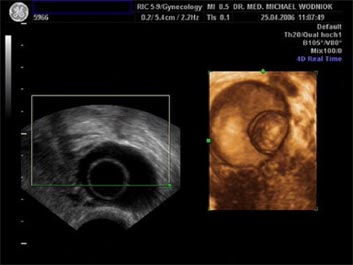

Hochauflösende Ultraschalluntersuchungen in Kombination mit der 3D-4D Technik werden in unserer Praxis routinemäßig durchgeführt. Dabei werden im Rahmen der Vorsorgeuntersuchung, sowie bei reinen vorsorglichen Ultraschalluntersuchungen auf Wunsch, auffällige Tastbefunde und noch unentdeckte Befunde weiter sonografisch abgeklärt. Bei zweifelhaften Befunden der Brüstdrüsen oder von Organen der inneren Genitalien kann der zusätzliche Einsatz der Farbdopplertechnik sehr hilfreich sein. Dabei stellt diese Technik bildlich sehr genau den Blutfluss, die Flussgeschwindigkeit, den Blutflusswiderstand sowie die Blutflussrichtung aller Blutgefässe dar. Die Interpretation dieser Ergebnisse fließt als zusätzlicher „Marker“ in die Entscheidung für das weitere klinische Vorgehen ein. Ein zunächst als völlig unauffällig eingestufter Ultraschallbefund eines zystischen Befundes im Eierstock wird bei einem unerwartet auffälligen Blutfluss an der inneren Zystenwand eine zeitnahe weitere Abklärung zu Folge haben. ![]() ![]() ![]() ![]() |